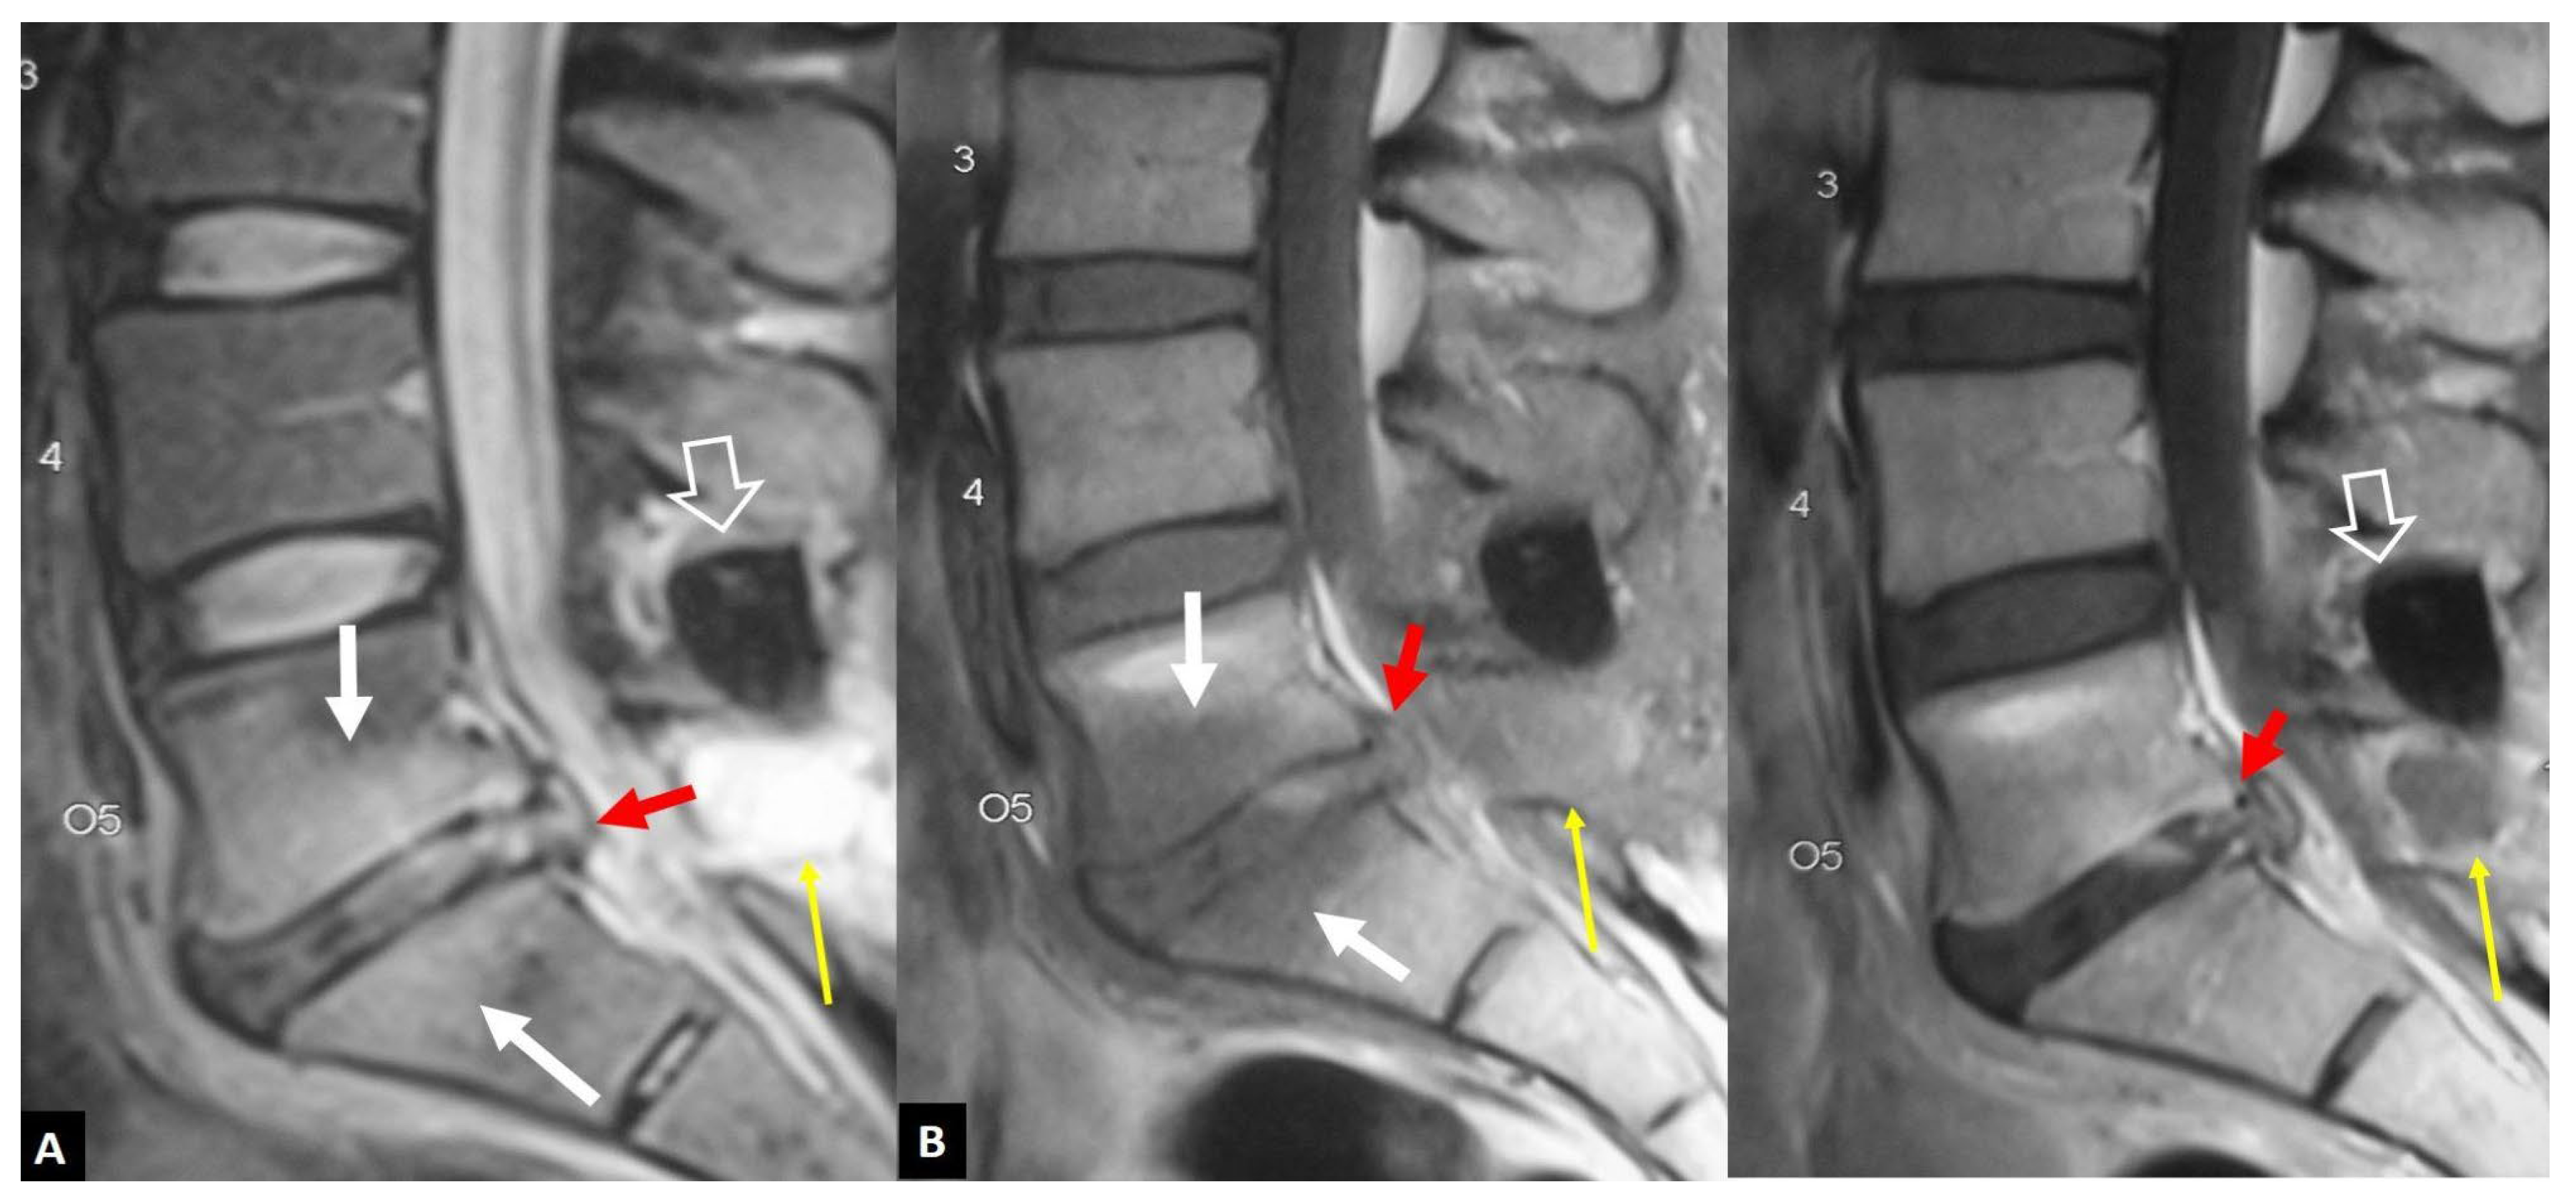

1. a.iv. Destructive Spondyloarthropathy

1. a.v. Crystal Deposition